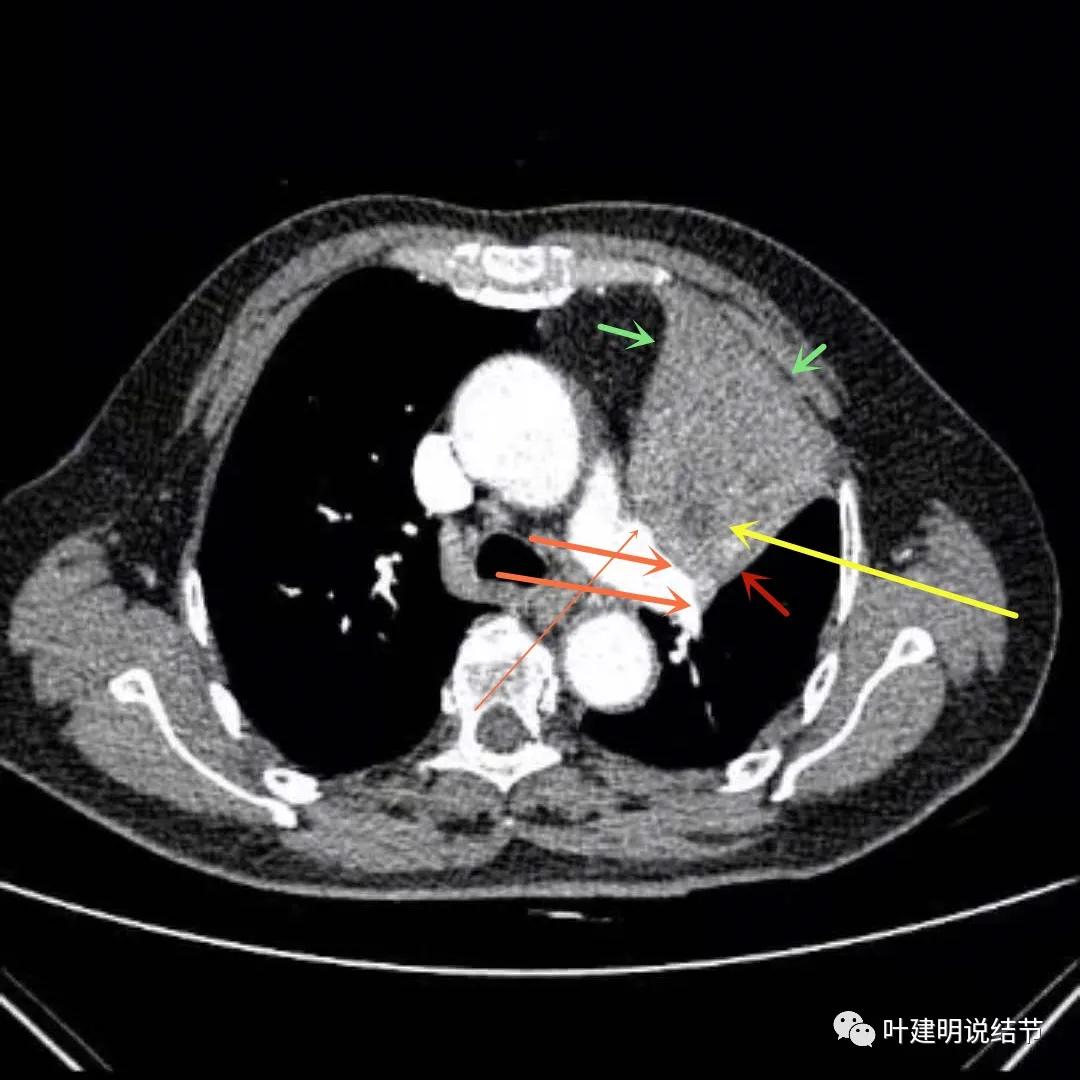

上图绿色箭头所指区域考虑为肺不张,红色示肿瘤处且有不均质与膨胀性,桔色细箭头所指处是被肿瘤包绕的肺动脉分支起始部,粗桔色箭头示肺动脉与肿瘤间紧密愈着,考虑有侵犯肺动脉